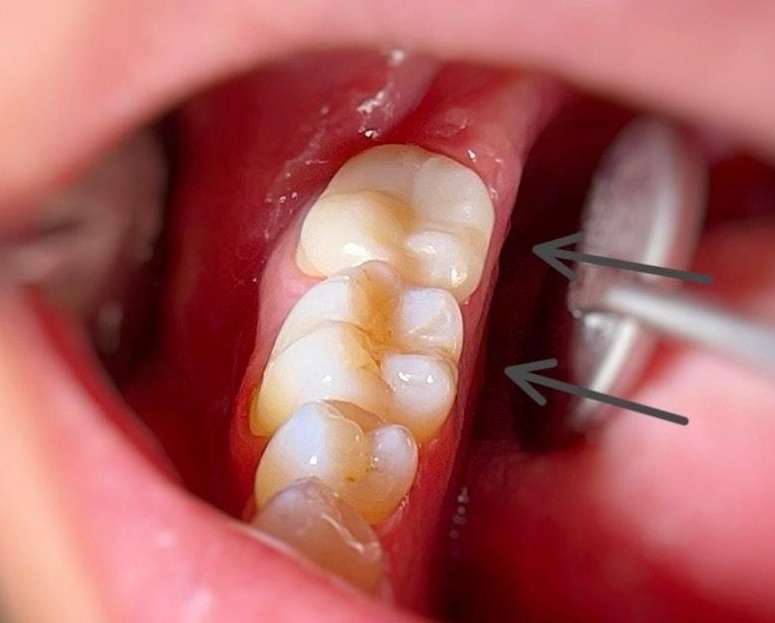

This patient came to our dental office in Charlotte because most of the chewing surface on one of their teeth had fractured, and their old silver filling was breaking down. Dr. Shirman placed a CEREC Same-Day crown to protect the tooth and restore its strength.